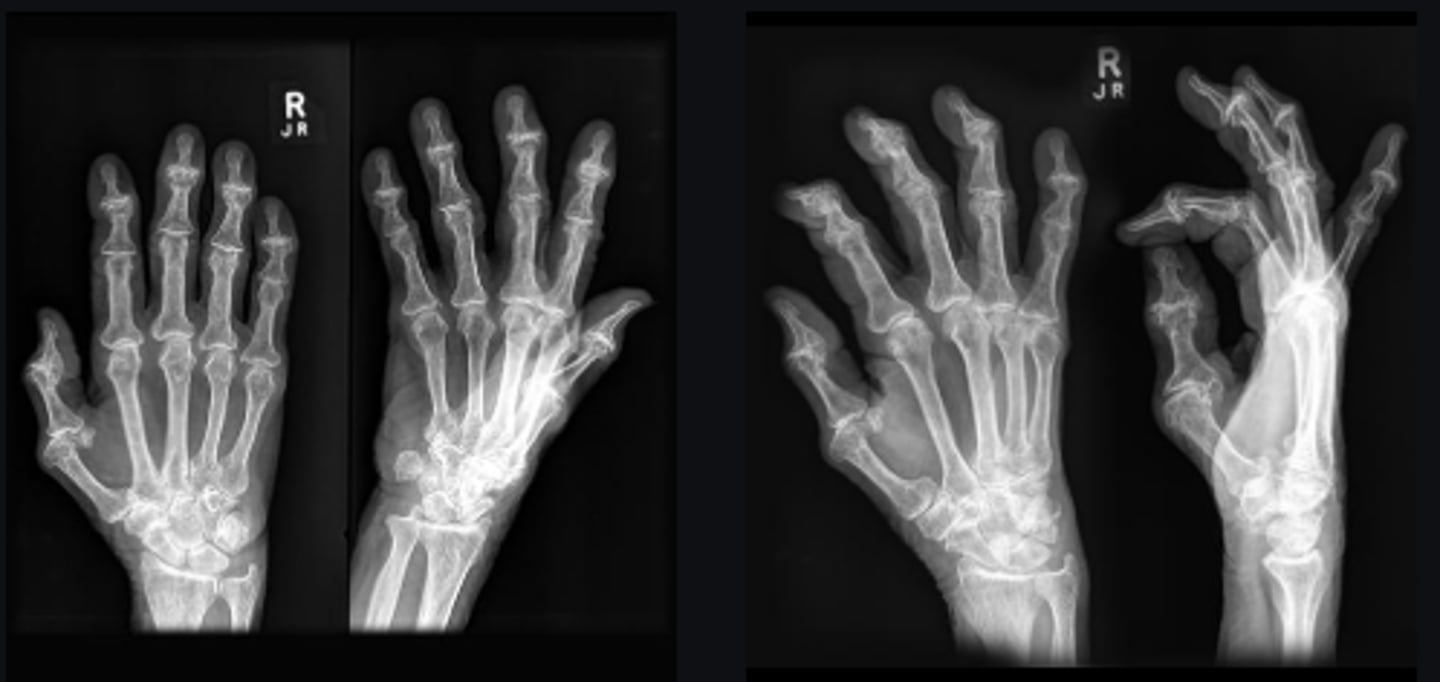

DIPs

Joint

Yes

Joint space narrowed?

Non-uniform

Uniform/non-uniform joint narrowing

No

Periarticular erosions

Osteophytes

A little bit

Subchondral cysts

Subchondral sclerosis

Periarticular osteopenia

Not a lot

Soft tissue swelling

Intra-articular calcification

Joint ankylosis

Extra-articular calcification/osseous bodies

Subluxation

Dislocation/diastasis

Degenerative

Category of disease

Osteoarthrosis

Diagnosis?

Heberden's nodes

Clinically, what may be noted by inspecting the involved joints?

- PIPs and DIPs involved

- Thick/swollen hand

- Gull-wing deformity

- Osteophytes

Describe findings

Erosive osteoarthritis

Middle-aged females

What patient population generally gets this disease?